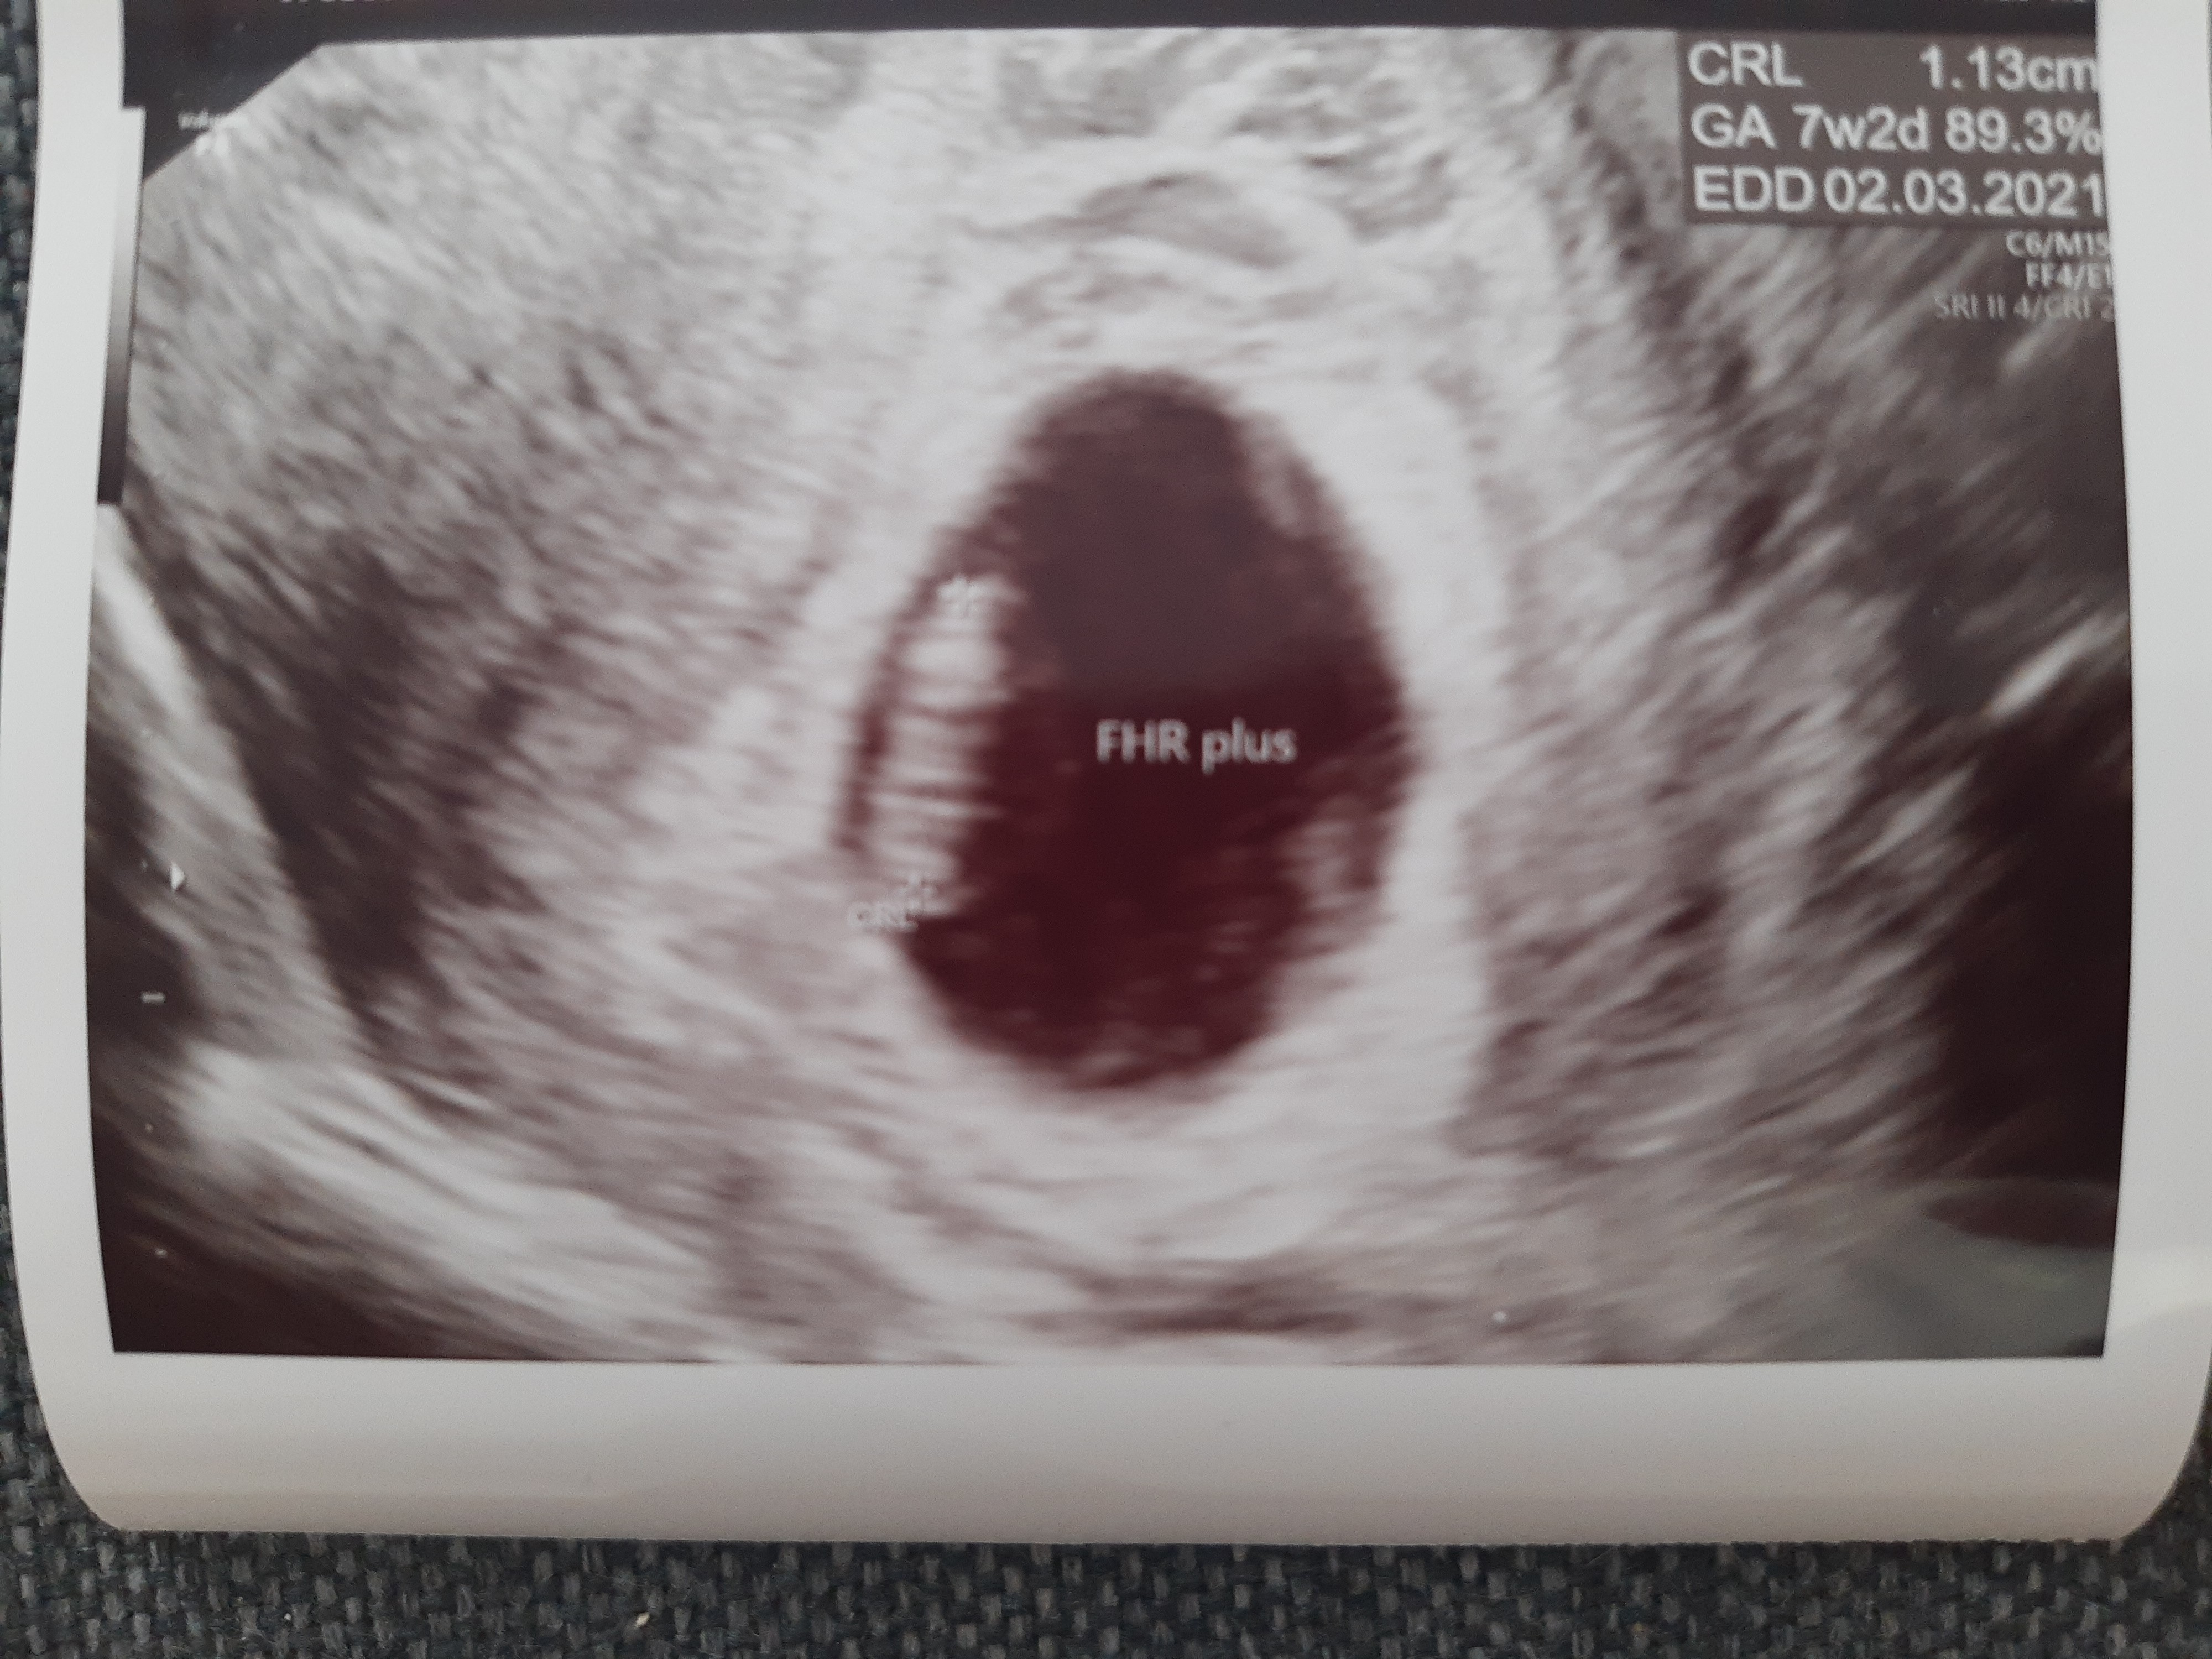

Ja po wizycie, tętno 153, płód rozwija się zgodnie z wiekiem ciąży 7tc2dc. Wg Pani doktor jest ok, nie widzi nieprawidłowości w samej ciąży. Ale mam ponoć mocną infekcje pochwy (czego wogòle nie czuje) i krwiaka. Mam prac duphaston i globulki, 27.07 mam znowu przyjść. Zakaz współżycia, sprzątania. Tylko leżeć leżeć i leżeć.

• IMG_20200716_152550975.jpg

1,9 MB · Wyświetleń: 97